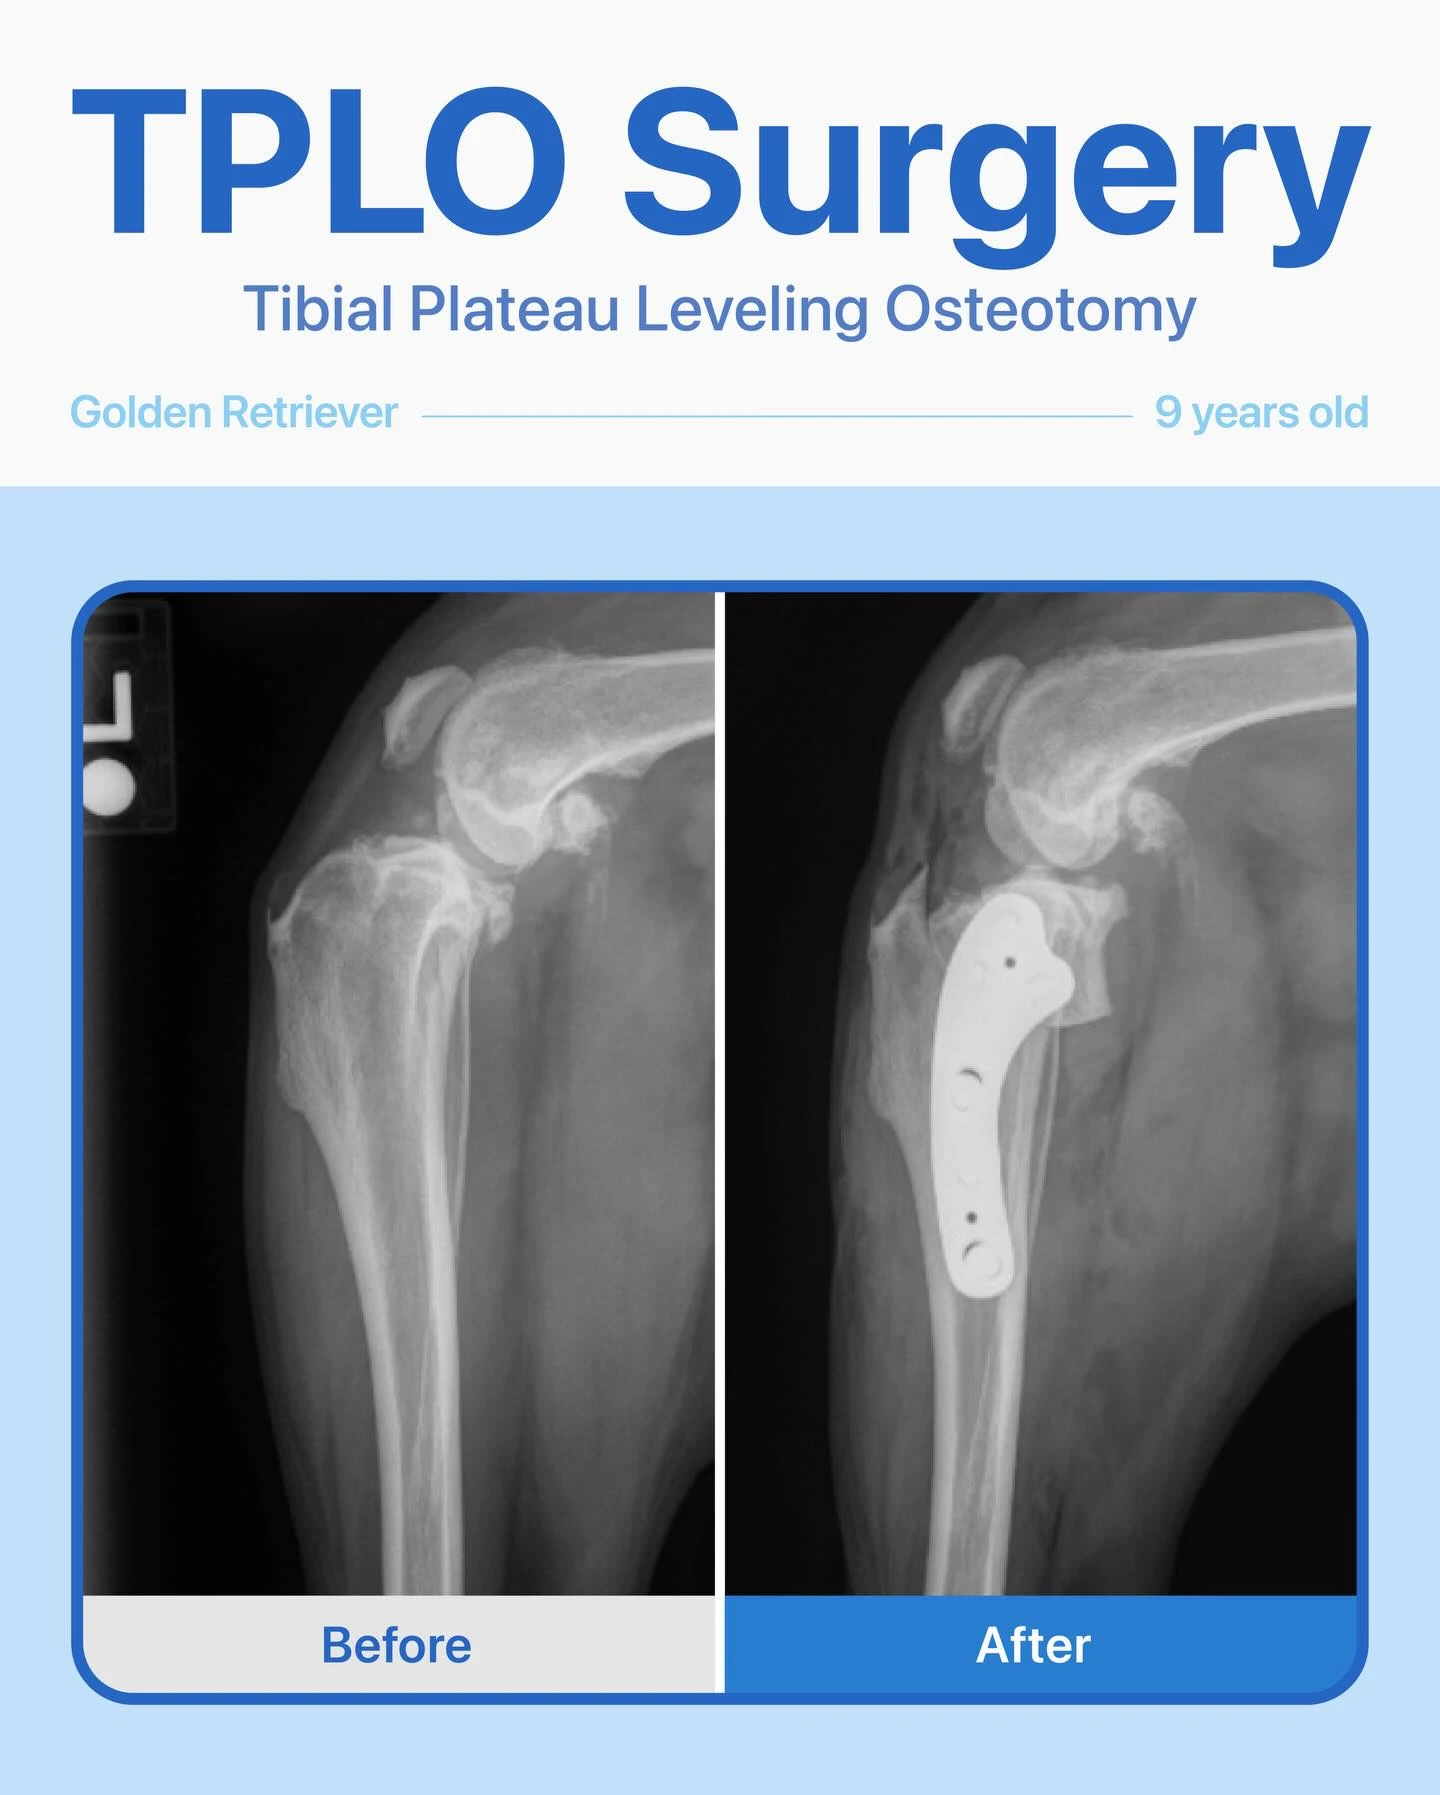

TPLO – Cavalier

This sweet 4-year-old female Cavalier King Charles Spaniel had been limping on her right back leg for about a year. Her owner noticed the leg looked thinner than the other and that she would yelp when we touched near her hip.

After radiographs, we confirmed a cruciate ligament tear, and she underwent a TPLO surgery.

The surgery went smoothly, and she’s healing wonderfully! We’re so … Read moreTPLO – Cavalier